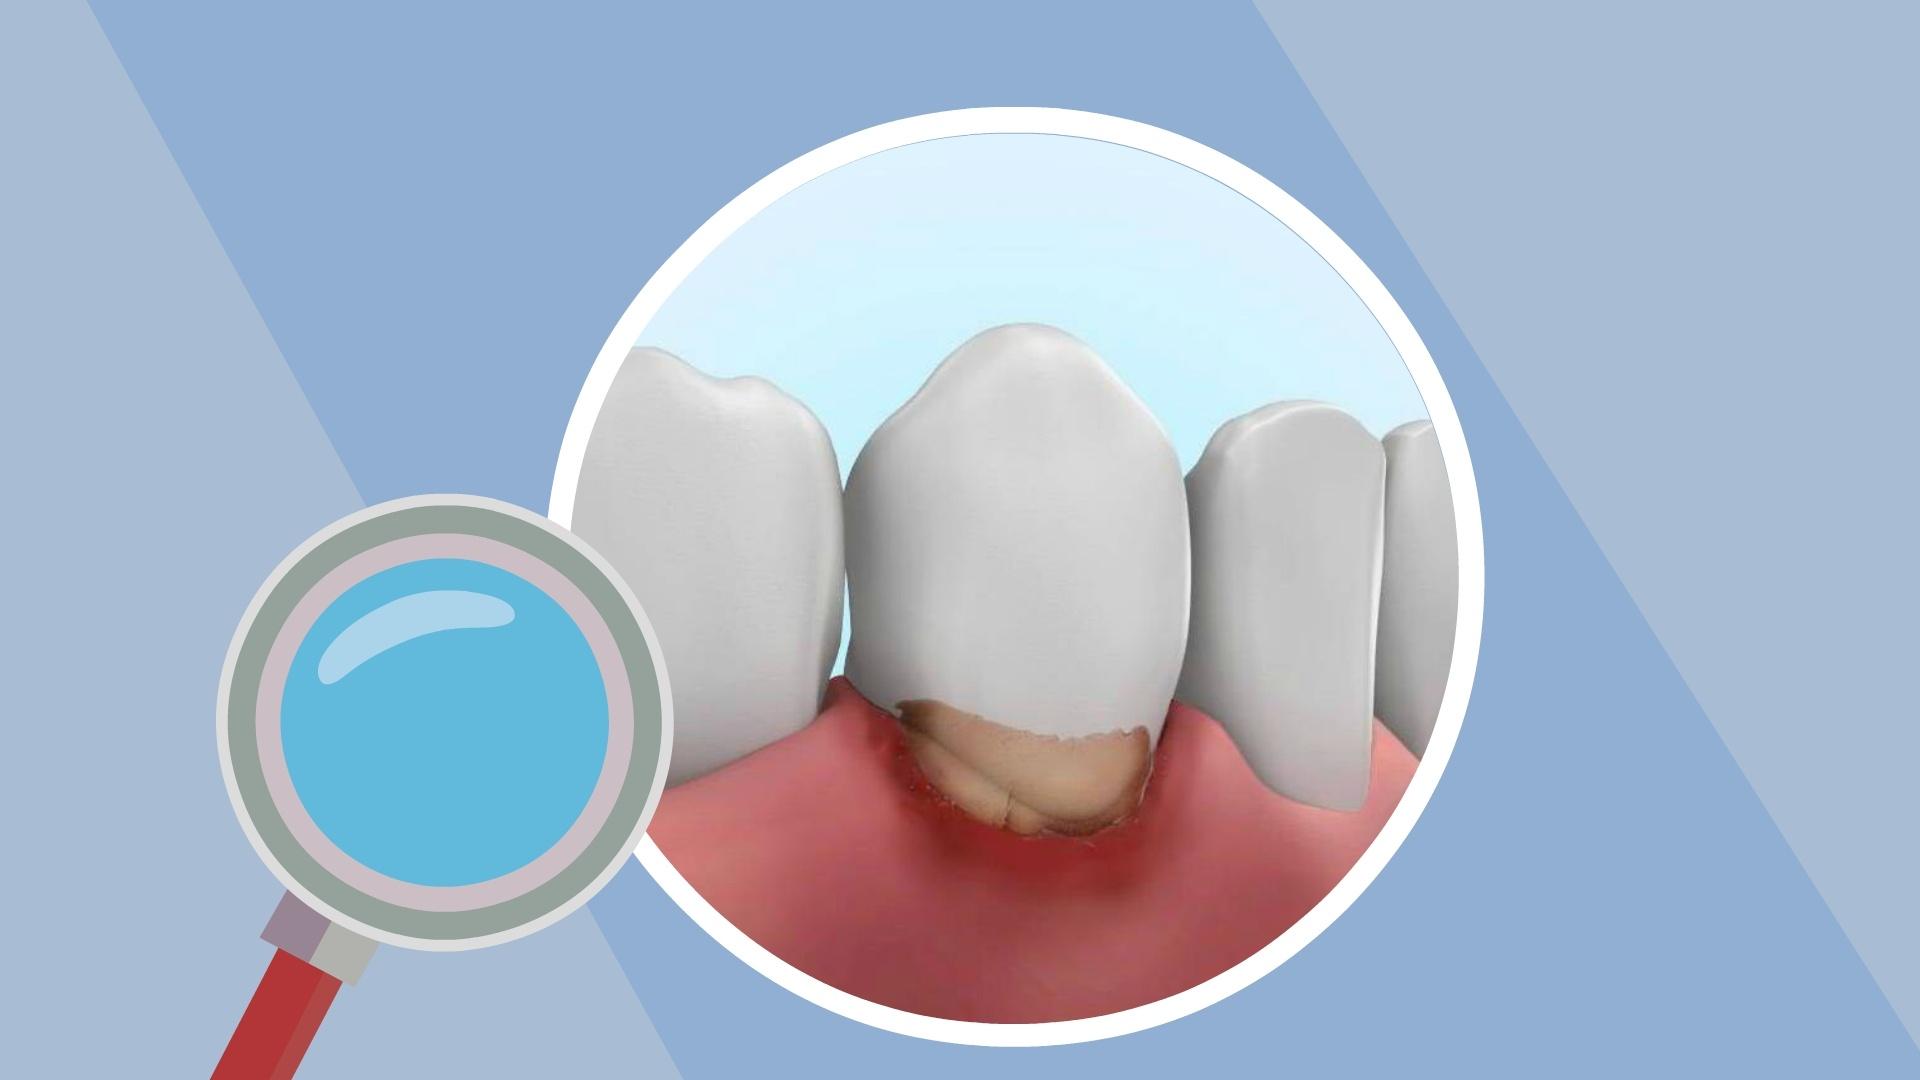

牙龈炎、牙周炎有什么区别?

牙齿变长牙缝变宽...注意!你的牙龈正在萎缩!